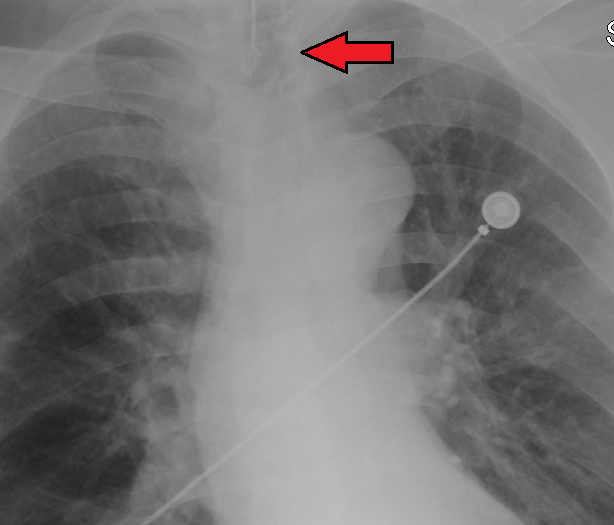

기관 튜브가 제 위치에 있는지 확인하기 위해 여러 방법을 사용한다. 캡노그래피는 기관 내 튜브 설치 확인을 위한 골드 스탠다드로 사용되고 있다. 튜브의 위치는 흉부 X선 촬영으로도 확인할 수 있는데, 기관 분기부에서 약 2cm 위에 위치하는 것이 이상적이다.

적절한 위치에 있는 기관 튜브의 원위단은, 기관 분기부에서 약 2cm 위에 위치하며, 이는 흉부 X선 촬영으로 확인할 수 있다. 기관이 기관 분기부보다 너무 깊이 들어가면, 기관 튜브의 선단이 우측 주 기관지 안으로 들어갈 수 있다 ('''한쪽 폐 삽관'''이라고 불린다). 이 상황에서는, 좌측 폐가 환기에 관여할 수 없게 되어, 환기 혈류 불균형에 의한 저산소혈증에 빠질 수 있다.

적절하게 위치한 기관 튜브의 팁은 쇄골 사이의 전후면 흉부 방사선 사진에서 중간 기관에 위치한다. 튜브의 적절한 직경은 약 25cm 수압에서 약간의 누출이 발생하는 직경이다. 기관 내 튜브의 적절한 내경은 아이의 새끼손가락과 대략 같은 직경으로 추정된다. 기관 내 튜브의 적절한 길이는 아이 입의 모서리에서 귓구멍까지의 거리를 두 배로 하여 추정할 수 있다. 생후 1년 이상 된 정상적으로 영양 상태가 좋은 어린이의 경우, 기관 내 삽관에 적절한 직경과 깊이를 추정하기 위해 두 가지 공식이 사용된다. 튜브의 내경(mm)은 (환자의 나이 + 16) / 4이고, 적절한 삽입 깊이(cm)는 12 + (환자의 나이 / 2)이다.